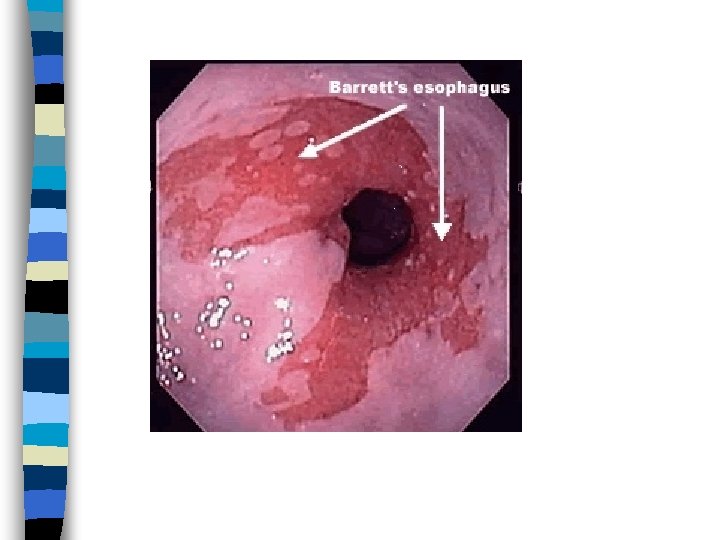

Barrett’s Esophagitis n Normal stratified squamous epithelium of distal esophagus replaced by: – Metaplastic, columnar, glandular intestinelike mucosa n Can give rise to adenocarcinoma n Warrants frequent surveillance by endoscopy